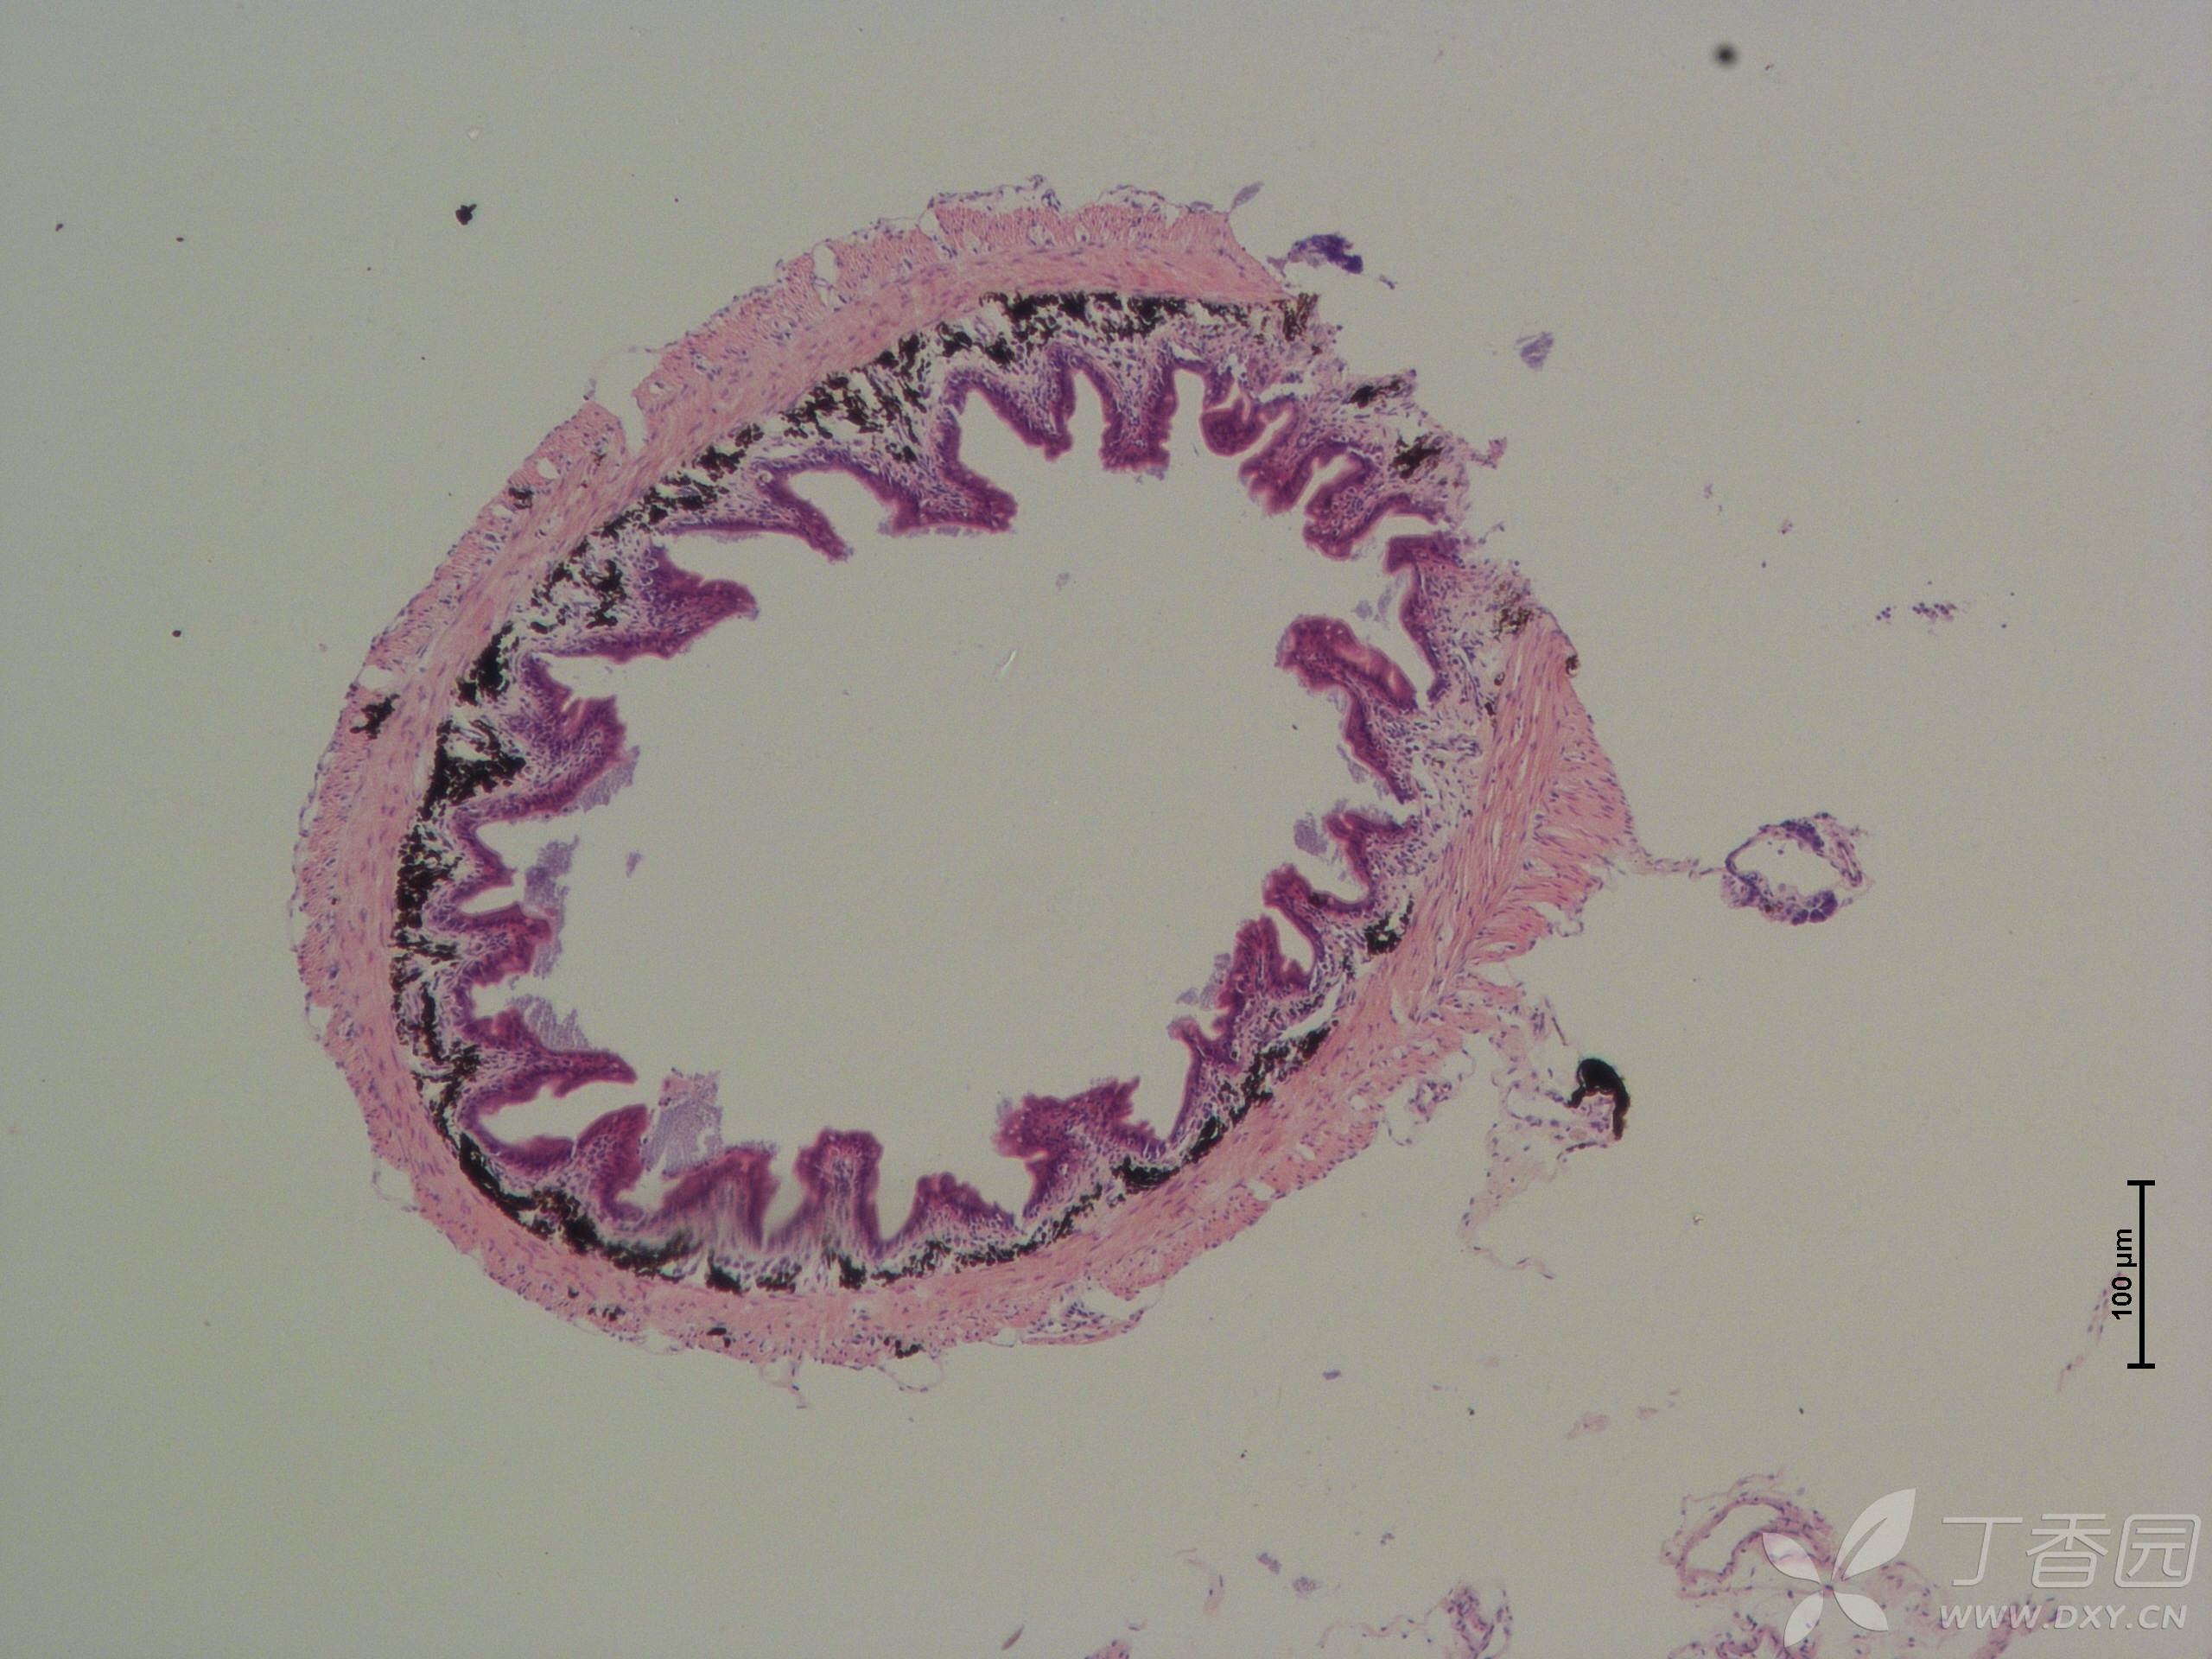

鱼类肠道he切片,求大佬指点